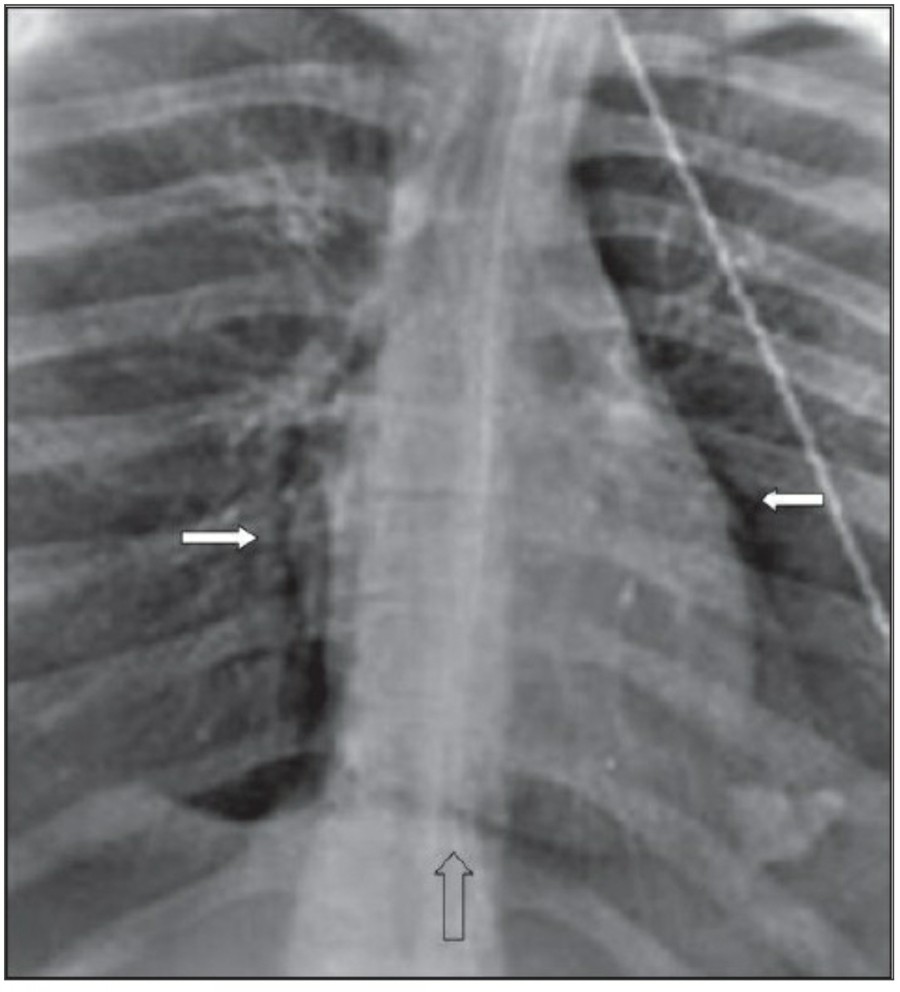

Subcutaneous emphysema는 드물지 않으며 주로 drain이나 다른 device의 percutaneous intrathoracic placement 시 발생한다. Fascail plane을 따라 air dissection이 발생하는데 임상적으로 의미가 없는 경우가 많다.

Subcutanoeus emphysema는 pneumomediastinum과 관련이 있을 수 있다. 하지만, isolated cervical subcutaneous emphysema가 있을 경우에는 upper airway 손상에 대한 평가가 필요한데, 특히 difficult intubation이나 nasogastric tube insertion 후에 발생할 수 있다. Chest X ray 상에서 subcutaneous emphysema 소견은 명확하다; 하지만 주로 pectoralis region의 muscle bundle 사이에서 발생하는 fascial plane의 air dissection은 lung prehncyme의 변화를 가리곤 하며, pneumothorax의 발견도 어렵게 만든다.

중환자에서 pneumothorax의 진단은 종종 supine radiograph에서 내릴 수 있다. Supine position에서 공기는 anteromedial 방향으로 모이게 되는데, apical air collection이 있을 경우 large pneumothorax가 있음을 시사한다. 공기는 lung과 diaphragm 사이의 subpulmonic location에 trap 되어 있을 수도 있다. 공기가 costophrenic sulcus로 anterolateral extension 될 경우, 이 costophrenic sulcus의 radiolucency를 증가시키는데, 이를 deep sulcus sign이라고 한다. Subpulmonic pneumothorax의 다른 특징으로 diaphragm의 superior surface와 IVC 윗부분이 뚜렷하게 보일 수 있다.

또한 Mediastitnal air는 major airway 손상으로 인한 leakage나 retroperitoneum으로부터 fascial plane을 따른 air dissection에 의해 발생하기도 한다. Pneumomediastinum은 목까지 공기가 진행이 가능하고, pneumopericardium은 이와는 다르게 심장의 밑 부분으로 진행한다. Pneumomediastium은 일반적으로 무증상이지만, 간혹 청진 시 restrosternal crunch가 들릴 수 있다. Chest X ray상에서 공기가 major vessel 주변이나 SVC의 medial border, azygos vein에서 surrounding lucency로 보일 수 있다. 또한 aortic knuckle, descending aorta, pulmonary artery의 윤곽으로 나타날 수도 있다. Posteromedial pneumomediastinum은 주로 esophageal rupture의 결과로 나타날 수 있는데, praspinal costophrenic angle과 left diaphragm의 praietal pleural로 air dissection이 가능하다. 이 결과 V-sign of Naclerio라고 불리는 V-shaped lucency가 발생한다.